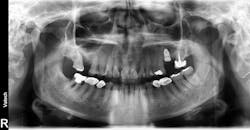

One recent retrospective clinical study investigated the correlation between low serum levels of vitamin D and early dental implant failure. This study evaluated 885 patients who had been treated with 1,740 fixtures. Patients with vitamin D deficiency (serum levels of vitamin D <10 ng/mL) showed an early implant failure rate of 11.1%, compared to a failure rate of 2.9% in patients with normal levels of the vitamin (>30 ng/mL).8 The authors concluded that in cases of unknown failure, serum levels of vitamin D should be examined, and the operator may be advised to administer vitamin D weeks to months prior to implant surgery (figures 3 and 4).